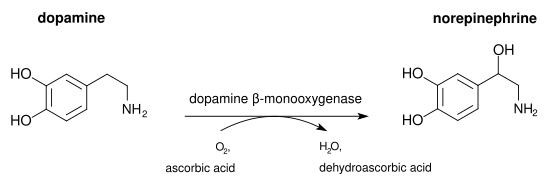

Dopamine beta-hydroxylase (DBH), also known as dopamine beta-monooxygenase, is an enzyme (EC 1.14.17.1) that in humans is encoded by the DBH gene. Dopamine beta-hydroxylase catalyzes the conversion of dopamine to norepinephrine.

The three substrates of the enzyme are dopamine, vitamin C (ascorbate), and O2. The products are norepinephrine, dehydroascorbate, and H2O.